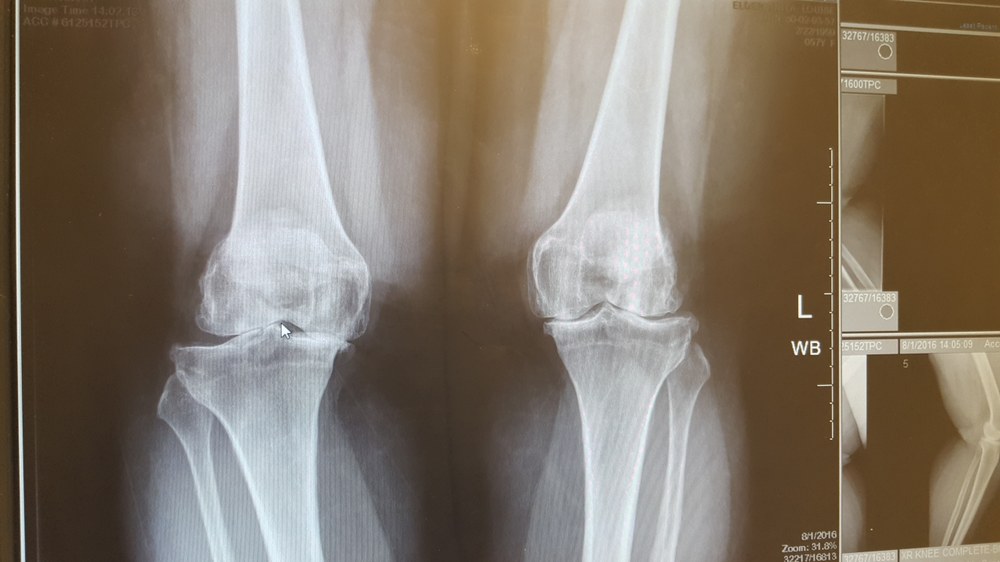

X-Rays on knees before surgery - bone on bone and off-set